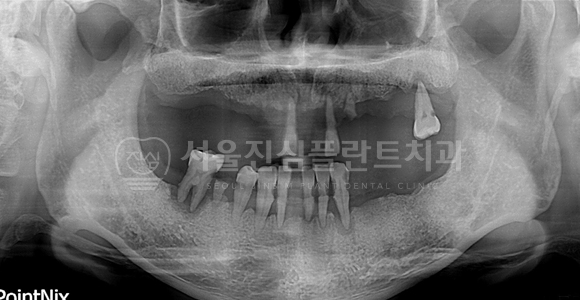

BEFORE

AFTER

상악동 거상 측방접근 + 상악 전치부 고난이도 뼈이식